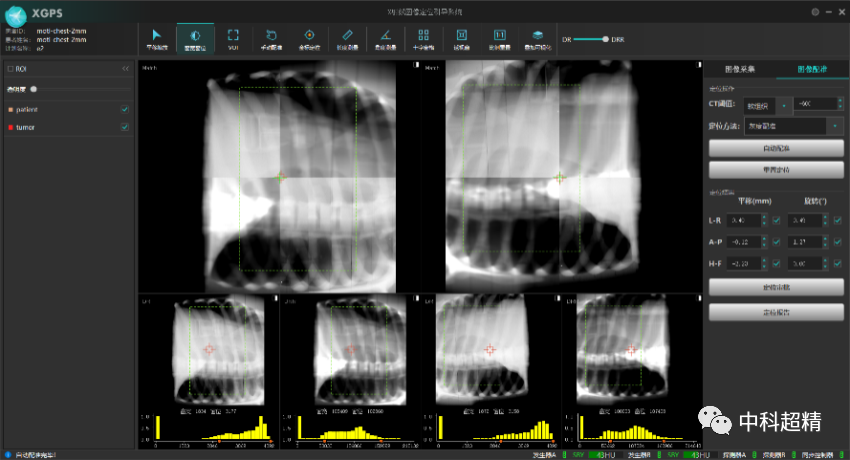

“麒麟刀·木” X射線圖像引導系統

(KylinRay-XGPS)

KylinRay-XGPS是面向腫瘤放射治療的圖像引導系統,主要基于透視成像對腫瘤患者放射治療過程實施精確定位,是中科超精在精準照射領域布局的另一重磅產品。該系統采用KV級透視成像和圖像智能配準技術,基于放射治療計劃以及三維CT圖像生成DRR圖像與采集投影圖進行2D-3D圖像配準,精確探測出 6個自由度的擺位誤差,真正實現了對患者在每個分次的高質量圖像引導。此產品可以獨立安裝,無需與直線加速器建立電氣連接,可適應各種主流加速器型號以及不同結構的機房,并幫助廣泛的用戶以最低的成本實現圖像引導的放射治療。